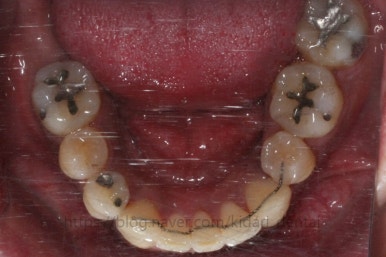

부산치아교정 키다리아저씨치과에 처음 내원 당시의 입안 모습입니다.

여러 가지 문제점이 있는데 하나씩 살펴볼게요.

치열이 많이 삐뚤하네요.

많이 삐뚠 상태에서 장기간 사용하다 보면 안좋은 방향으로 치아가 힘을 받게 되고 마모나 치아 목부분 패임이 심해집니다.

양치가 힘들어요. 양치가 힘들다 보니 세게 닦게 되고 치아 손상은 더 심해져요. 25세의 나이였는데 나이에 비해서 치아나이가 굉장히 많은거죠.

화살표 부분에 원래 송곳니가 있어야 되는데 보이질 않네요. 결손치아일 수도 있고 매복치아일 수도 있겠어요.

왼쪽 위 어금니도 한 개가 없어서 빈공간이 약간 남아있어요.

왼쪽 아래 작은 어금니는 아래쪽으로 많이 꺼져있네요.